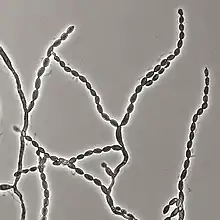

Cladophialophora bantiana exhibits predominantly hyphal growth both in vivo and in vitro.[5] The normal morphology consists of dark coloured largely unbranched, wavy chains of conidia, individually 5–10 µm in length.[5] The dark colour is due to the presence of the dark pigment melanin.[6] Hyphae are septate, as is the case for species belonging to the phylum ascomycota.[1] In samples isolated from cerebral tissue compared to cultured samples, a predominance of unbranched conidial chains and absence of conidiophores has been reported.[5][6] In culture, the colony is black with a velvety texture or dark grey in colour, depending on the type of agar medium it is grown on.[2] Cladophialophora bantiana has been reported to grow in culture under temperatures ranging from 14-42 °C with optimal growth around 30 °C.[2] Cladophialophora bantiana grows slowly in vitro, taking ~15 days to mature when grown at 25–30 °C.[1] Cladophialophora bantiana can be distinguished from other species of the genus Cladophialophora by the presence of the enzyme urease.[7]